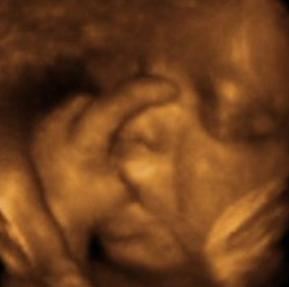

Scarsdale 3d 4d Ultrasound Studio Beautiful Beginnings 3d Imaging

Tlc Imaging 3d 4d Ultrasounds 7622 Farmsbury Dr Reynoldsburg Oh